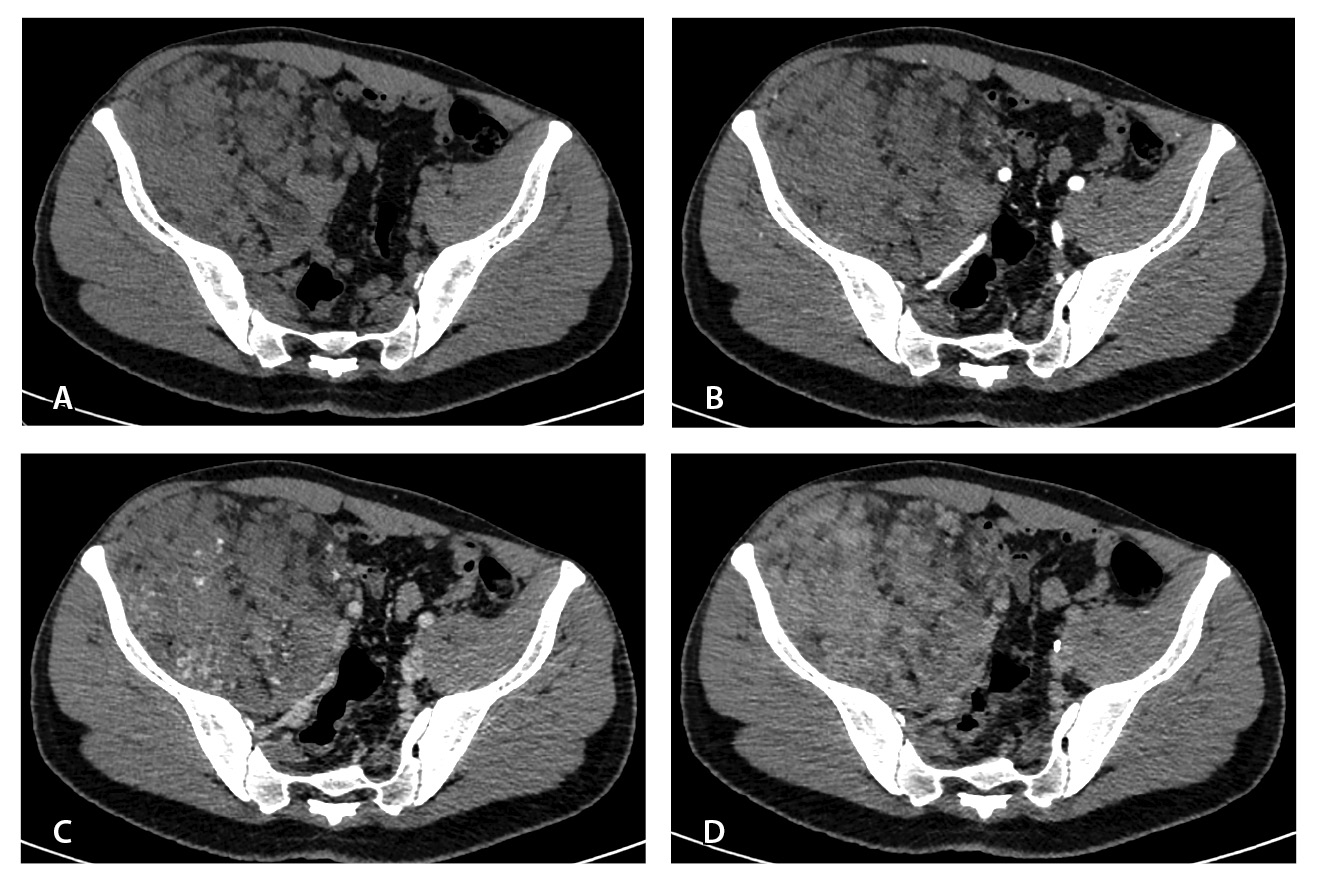

При контрольной томографии, проведенной на 5-е сутки после операции, забрюшинно справа определялась остаточная ткань опухоли размерами 125 × 81 × 90 мм. Резидуальный фрагмент прилегал к правой подвздошной кости, по ходу подвздошных сосудов, с распространением на переднюю поверхность правого бедра. Признаков экстравазации контрастного препарата не обнаружено (рис. 3).

Рис. 3. Мультиспиральная компьютерная томография органов брюшной полости и забрюшинного пространства с болюсным внутривенным контрастированием, венозная фаза. А – исследование до операции, Б – исследование после операции: резидуальный фрагмент образования (красная стрелка) тесно прилежит к подвздошной кости и подвздошным сосудам (головка синей стрелки)